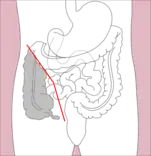

- Right hemicolectomy and left hemicolectomy refer to the resection of the ascending colon (right) and the descending colon (left), respectively. When part of the transverse colon is also resected, it may be referred to as an extended hemicolectomy.[5]

Right hemicolectomy

Right hemicolectomy Right extended hemicolectomy